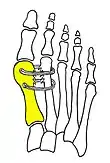

Syndesmosis procedure

Cerclage bone sutures

Fig. 2: Cerclage bone sutures

Fibrous connecting bridge to prevent recurrence

Fig. 3: Fibrous connecting bridge to prevent recurrence

Technique

Syndesmosis procedure addresses specifically the two fundamental problems of metatarsus primus varus deformity that gives rise to the bunion deformity. They are leaning and instability of the first metatarsal bone . Syndesmosis procedure uprights the leaning first metatarsal bone with strong binding sutures between it and the second metatarsal bone (Fig. 2) and then also stabilizes it uniquely by creating a fibrous connecting bridge between these two bones (Fig. 3, 4). First metatarsal bone can be readily realigned because by definition of the metatarsus primus varus deformity its first metatarsal is abnormally loose and mobile.